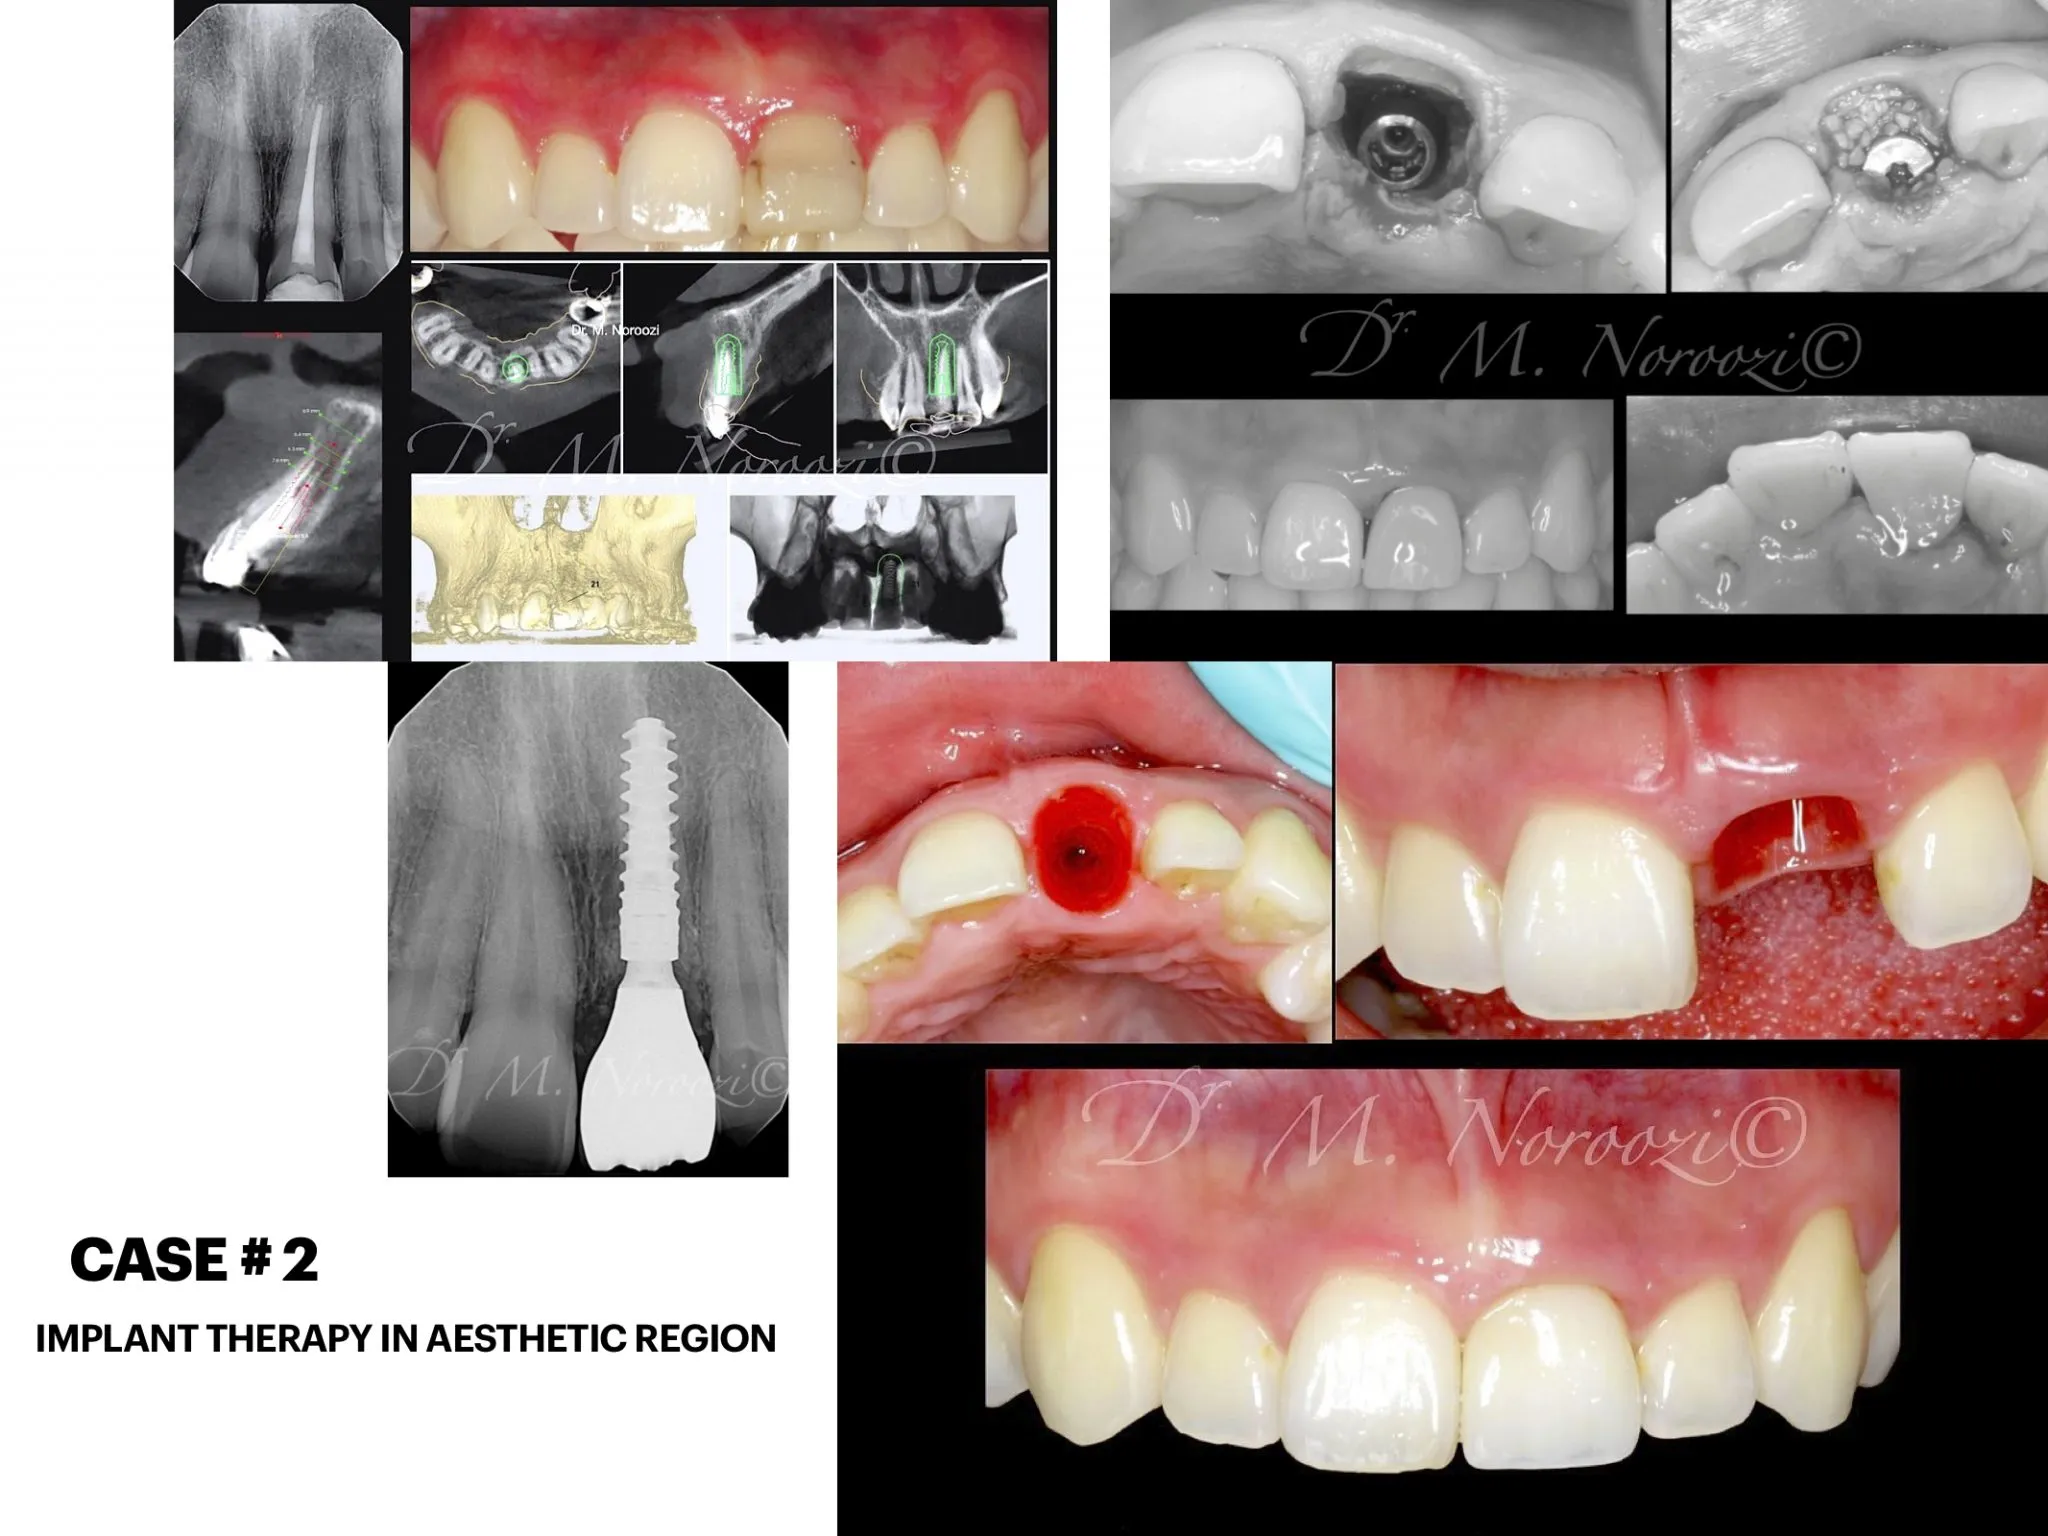

IMPrESS Perio Immediate upper front implants with partial extraction therapy, guided surgery and provisional and final crowns

Front Teeth Dental Implants in Vancouver

Front tooth implant Esthetic implant dentist Implant specialist IMPrESS Perio Implant Center Dr. M. Noroozi Implant Specialist

IMPrESS Perio Immediate upper front implants with partial extraction therapy, guided surgery and provisional crowns

Front Teeth Dental Implant Bridge by Vancouver Dr. Noroozi Implant Specialist